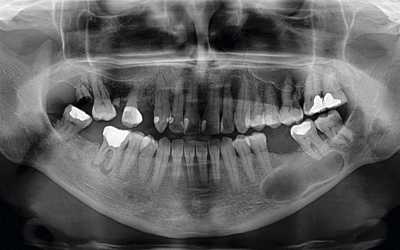

Для уточнения диагноза выполняют рентгенологическое исследование пораженного сегмента: рентгенографию бедренной кости, рентгенографию плечевой кости и т. д. На основании рентгенологической картины определяют фазу патологического процесса. В фазе остеолиза на снимке обнаруживается бесструктурное разрежение метафиза, соприкасающееся с зоной роста. В фазе отграничения на рентгенограммах видна полость с ячеистым рисунком, окруженная плотной стенкой и отделенная от зоны роста участком нормальной кости. В фазе восстановления на снимках выявляется участок уплотнения костной ткани или небольшая остаточная полость.

- Рентгенологическое обследование. Рентгенография и КТ челюстей, рентгенография и КТ придаточных пазух носа. Определенную диагностическую ценность может представлять сцинтиграфия, термография.

На ортопантомограмме доктор наблюдает полость сферической формы с четко очерченными контурами. На рентген-снимке можно разглядеть корень пораженного зуба с воспаленным периодонтом.

Предварительный диагноз стоматолог ставит сразу после проведения внешнего осмотра зубного ряда. Досконально изучить имеющуюся опухоль можно, используя метод рентгенографии. Тогда, глядя на снимок, доктор может понять, о каком виде опухоли идет речь, есть ли риски для пациента и что в себя должно включать предстоящее лечение.